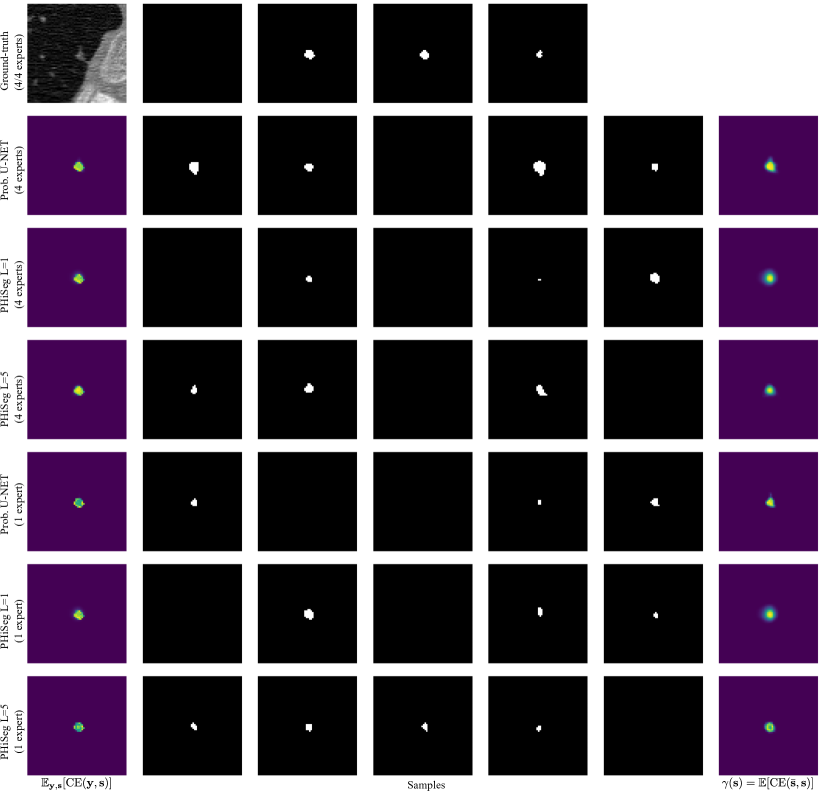

We evaluated the techniques in two experiments. First, we trained the methods using the masks from all available annotators, where in each batch we randomly sampled one annotation per image. We were interested in assessing how closely the distribution of generated samples matched the distribution of ground-truth annotations. To this end, we used the generalised energy distance where is 1 minus the intersection over union, i.e. , and are samples from the learned distribution , and ground-truth distribution [4]. The GED reduces the sample quality to a single, easy-to-understand number but, as a consequence, cannot be interpreted visually. Therefore, we additionally aimed to produce pixel-wise maps showing variability among the segmentation samples. We found the expected cross entropy between the mean segmentation mask and the samples to be a good measure, i.e. with the pixel position and the mean prediction. is statistically similar to variance with the L2-distance replaced by CE. However, we believe it is more suitable for measuring segmentation variability. Examples of our -maps along with sample segmentations are shown in Fig. 3. We quantify how well the -maps for each method predict regions with large uncertainty using the average normalised cross correlation (NCC) between the -maps and the CE error maps obtained with respect to each annotator:

We observed that when using all annotators for training, PHiSeg () produced significantly better and scores compared to all other methods. This can be observed qualitatively in Fig. 3 for a prostate slice with large inter-expert disagreements. Both, the prob. U-NET and PHiSeg () produced realistic samples but PHiSeg () was able to capture a wider variability. Furthermore, as indicated by the high values, PHiSeg’s () -maps were found to be very predictive of where in the image the method’s average prediction errors will occur. Similar results were obtained when training with only one annotator. We noticed that in this scenario the prob. U-NET may in some cases fail to learn variation in the data and revert back to an almost entirely deterministic behaviour (see fourth row in Fig. 3). We believe this can be explained by the prob. U-NET’s architecture which, in contrast to our method, allows the encoder-decoder structure to bypass the stochasticity. While our method also predicted smaller variations in the samples, they were still markedly more diverse. The lower performance of PhiSeg () indicates that using multiple resolution levels is crucial for our method. More samples for the prostate and LIDC-IDRI datasets can be found in Appendix B. From Tab. 1 it can be seen that no significant differences between the Dice scores were found for any of the methods (except PHiSeg’s ()), including the det. U-NET. From this we conclude that neither PhiSeg () nor the prob. U-NET suffer in segmentation performance due to their stochastic elements.

Appendix 0.B Additional Samples

Fig. 0.B.2 shows a thoracic lesion with disagreements regarding the shape of the lesion, while Fig. 0.B.3 is showing an example where the disagreement is over presence or absence of the lesion.